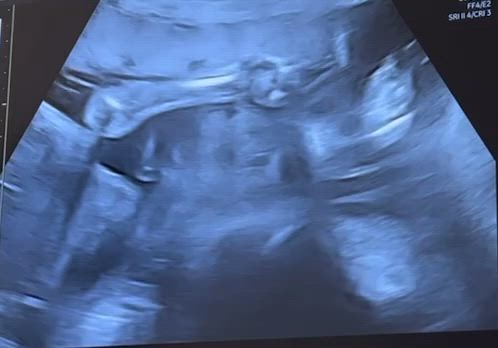

【妊婦健診④】24w6dお腹の張りが4日続く